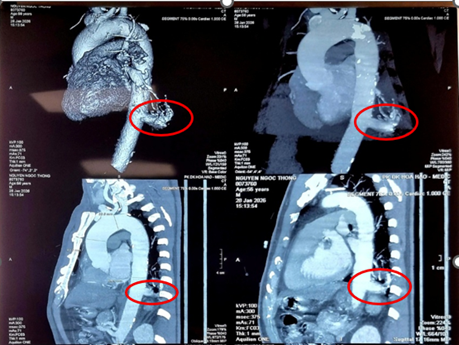

MSCT ngực cho thấy phổi biệt lập nội thùy trong thùy dưới phổi trái, có nhánh mạch máu nuôi lớn xuất phát từ động mạch chủ ngực. Ảnh: BV

Đáng chú ý, động mạch nuôi khối này xuất phát trực tiếp từ động mạch chủ ngực xuống có kích thước rất lớn với đường kính 17 mm, tiềm ẩn nguy cơ biến chứng nếu không được phát hiện và xử trí kịp thời.